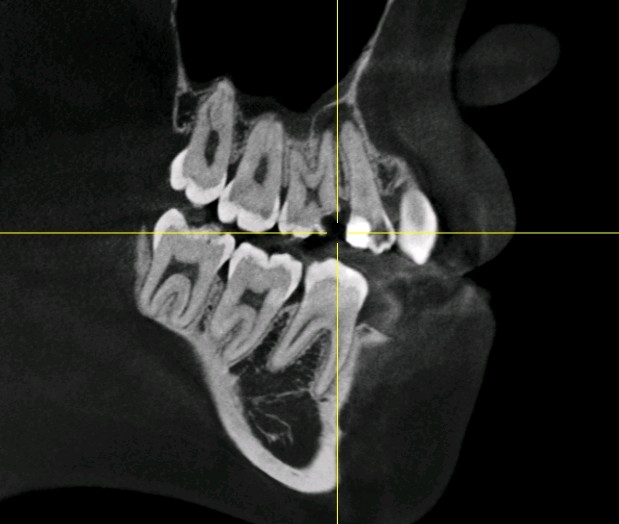

患者女,二十三岁,右上后牙食物嵌塞前来就诊。检查发现15。16,邻颌面大面积龋坏,牙体结构也发生了缺损,通过X线显示龋坏及髓,根尖大面积低密度影像。

治疗计划:根管治疗+纤维桩+高嵌体修复

术前